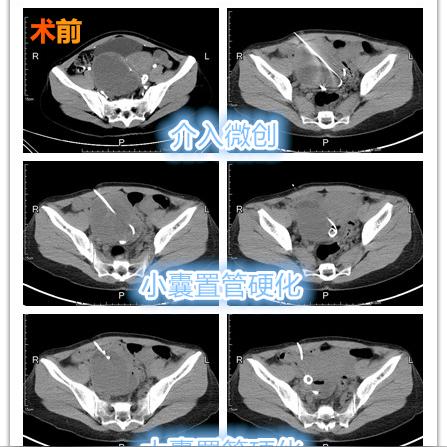

卵巢囊肿是指卵巢内出现的液体填充的囊状结构,大多数卵巢囊肿为良性,不会引起严重症状,部分卵巢囊肿可能需要治疗,因为它们可能引起疼痛、不孕或其他并发症。

腹腔镜手术是目前治疗卵巢囊肿最常用的方法之一,通过腹腔镜技术,医生可以在不开刀的情况下,通过微小切口进行手术,从而减少对患者的创伤,据统计,约90%的卵巢囊肿患者通过腹腔镜手术可以成功治疗。

射频消融治疗是一种新型治疗卵巢囊肿的方法,通过射频能量将囊肿内的液体转化为气体,从而达到消除囊肿的目的,此方法具有创伤小、恢复快的优点,近年来,射频消融治疗在卵巢囊肿治疗中的应用逐渐增多。

激光治疗是近年来兴起的一种治疗卵巢囊肿的方法,通过激光技术,使囊肿内的液体逐渐被吸收,从而达到缩小甚至消除囊肿的目的,激光治疗具有无创、痛苦小的优点,尤其适用于对手术有顾虑的患者。